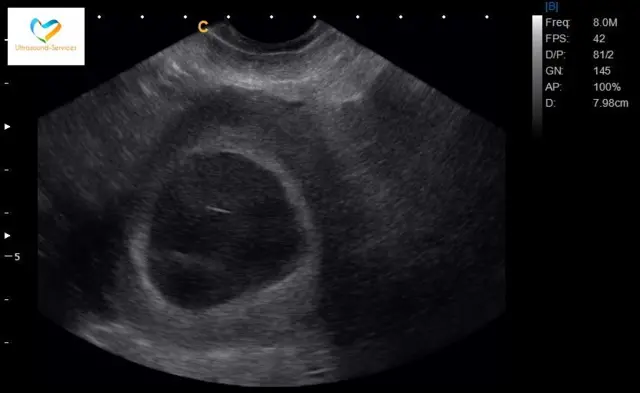

Pero esta vez la imagen del monitor no auguró nada bueno. "Allí solo se veía la cavidad, como una tumba negra hueca", dice. "Mi ginecóloga se quedó en silencio y entendí que algo malo pasaba".

La especialista le dijo que aquello parecía un embarazo anembrionario, también llamado huevo huero, que ocurre cuando el embrión nunca se desarrolla o deja de desarrollarse, es reabsorbido y deja un saco gestacional vacío. Es, en otras palabras, un embarazo sin bebé.